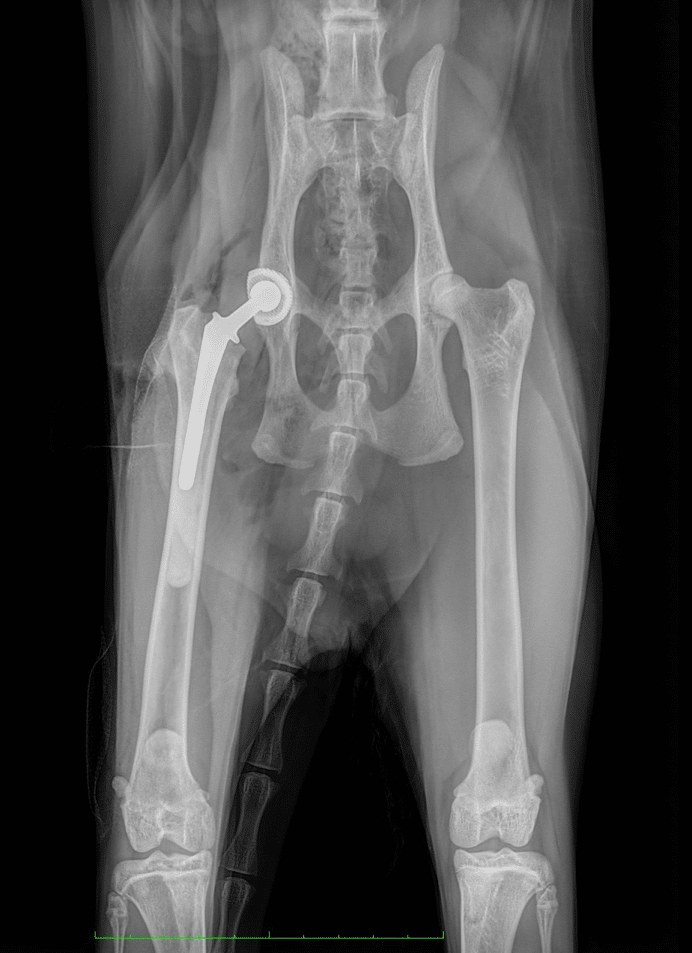

Après avoir discuté des avantages et des inconvénients des différentes options avec les propriétaires, Shining a été opéré en posant une PTH Biomedtrix, utilisant une cupule acétabulaire non cimentée et une tige fémorale cimentée. Les radiographies postopératoires ont montré un positionnement correct des implants et, après deux jours d’hospitalisation pour le contrôle de la douleur, l’administration d’antibiotiques et la perfusion, Shining est sorti du CHV et ses propriétaires ont reçu des instructions sur la gestion de la période post-opératoire. Le suivi réalisé à 2, 4 et 8 semaines a montré une récupération progressive de la mobilité et de la masse musculaire, et le chat a pu reprendre une activité physique complète 8 semaines après l’opération sans aucun signe de gene ou de reduction de la mobilité.

En conclusion, la prothèse totale de hanche est un traitement chirurgical efficace, avec une très bonne satisfaction des propriétaires et grâce auquel Shining a pu retrouver une mobilité complète comparable à celle qu’il avait avant sa pathologie